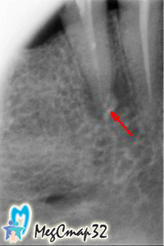

К нам обратилась пациентка с жалобой на боль в зубе при жевании.

После компьютерной диагностики было обнаружено воспаление в области верхушки корня.

В первое посещение был снят протез, распломбирован ранее

некачественно запломбированный канал зуба

в очаг инфекции выведен противомикробный препарат (рис. 1).